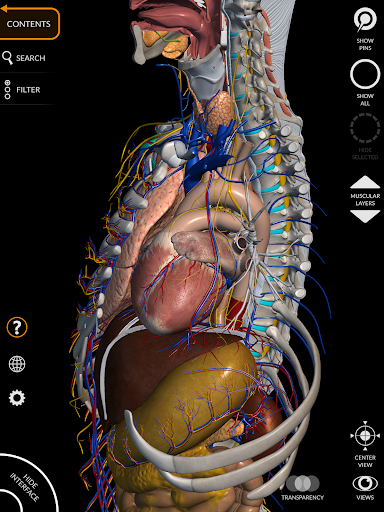

"Anatomía - Atlas 3D" permite estudiar la anatomía humana de forma fácil e interactiva.

A través de una interfaz sencilla e intuitiva es posible observar cada estructura anatómica desde cualquier ángulo.

Los modelos anatómicos 3D son especialmente detallados y con texturas de hasta una resolución de 4k.

La subdivisión por regiones y las vistas predefinidas facilitan la observación y el estudio de partes individuales o grupos de sistemas y las relaciones entre los diferentes órganos.

MODELOS ANATÓMICOS 3D

• Sistema musculoesquelético

• Sistema cardiovascular • Sistema

nervioso • Sistema respiratorio • Sistema digestivo • Sistema urogenital (masculino y femenino) • Sistema endocrino • Sistema linfático • Sistema ocular y auditivo CARACTERÍSTICAS • Interfaz sencilla e intuitiva • Rotar y hacer zoom en cada modelo en el espacio 3D • Opción para ocultar o aislar uno o varios modelos seleccionados • Filtro para ocultar o mostrar cada sistema • Función de búsqueda para encontrar fácilmente cada parte anatómica • Función de marcador para guardar vistas personalizadas • Rotación inteligente que mueve el centro de rotación automáticamente • Función de transparencia • Visualización de músculos a través de niveles de capas desde las superficiales hasta las más profundas • Al seleccionar un modelo o un pin, aparece el término anatómico relacionado • Descripción de los músculos: origen, inserción, inervación y acción • Mostrar/ocultar interfaz de usuario (muy útil con pantallas pequeñas) MULTILINGÜE • Los términos anatómicos y la interfaz de usuario están disponibles en 11 idiomas: latín, inglés, francés, alemán, italiano, portugués, turco, ruso, español, Chino, japonés y coreano • Los términos anatómicos se pueden mostrar en dos idiomas simultáneamente REQUISITOS DEL SISTEMA • Android 8.0 o posterior, dispositivos con al menos 3 GB de RAM Reversi